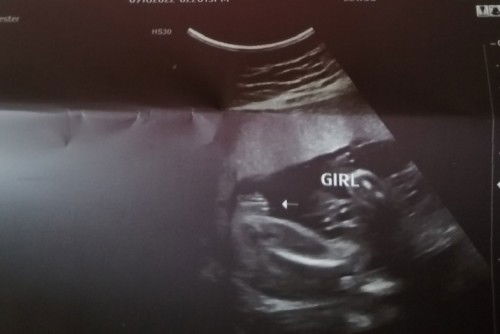

Gender. SURE NA PO BA ITO

Mga mii sure na ba eto Girl gender ng baby ko?